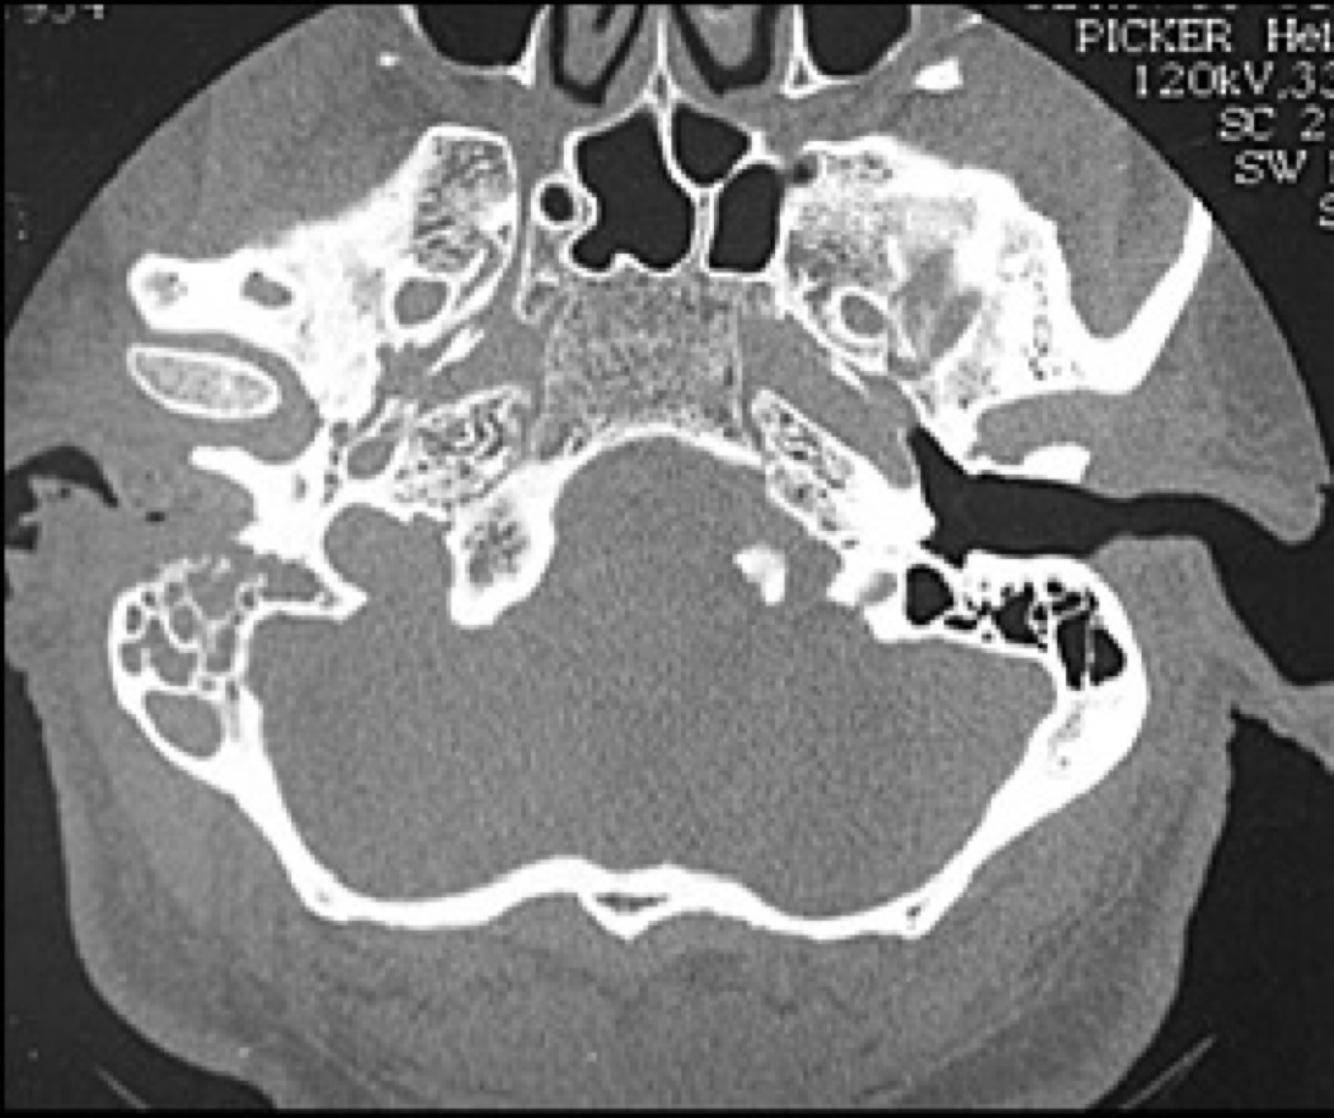

57M w/presents for evaluation of R-pulsation tinnitus that has been present for several mos. An audiogram shows normal hearing on the L and a moderate CHL on the R. Otoscopy on the R is shown in the image. CT images are also shown below. What is the diagnosis?

Tympanic paraganglioma tumors (glomus tympanicum) - arises from glomus body of the promontory along Jacobson’s n.

57M w/presents for evaluation of R-pulsation tinnitus that has been present Xooms. An audiogram shows normal hearing on the L and a moderate CHL on the R. Otoscopy on the R is shown in the image. CT images are also shown below. What is the most reasonable next step in management of his ear mass?

The dx is made clinically, and next step is further imaging w/MRI (provides superior soft tissue and vascular resolution).